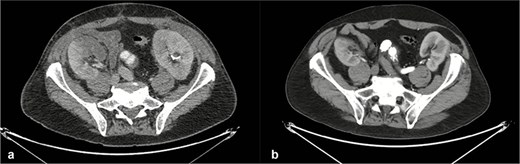

After 43 days of hospitalization, the patient underwent successful placement of a physician-modified endograft (PMEG) based on a 30/26 mm straight Zenith® endograft (Cook Medical, Bloomington, IN, USA), designed for two-vessel revascularization (celiac trunk and superior mesenteric artery). Preoperative planning was performed using 3mensio Vascular™ software (Pie Medical Imaging, Maastricht, The Netherlands), and bridging stents included VBX and BeGraft devices (8 × 39 mm and 8 × 37 mm for the celiac trunk; 6 × 59 mm and 6 × 57 mm for the superior mesenteric artery). The endograft was successfully deployed (Fig. 5) without intraoperative or postoperative complications (Figs 6 and 7). The patient recovered well and was discharged home in stable condition.

Axial computed tomography images of the thoracoabdominal region obtained before (a) and after (b) endovascular aortic repair. Postoperative imaging demonstrates patent renal arteries with preserved bilateral renal enhancement, consistent with maintained renal perfusion and function.